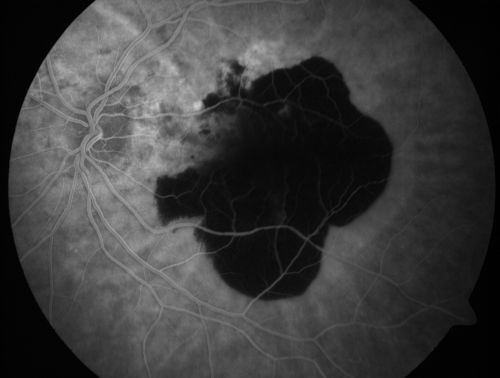

Wet AMD Fresh Submacular Hemorrhage - Displaced with Vitrectomy and Subretinal TPA

85-year-old woman has wet age-related macular degeneration in her better eye and she was reading with it until two days ago when she had sudden severe vision loss in the eye.  Her last injection with Avastin 2 weeks ago   20/160 (Pre-Surgical Displacement)